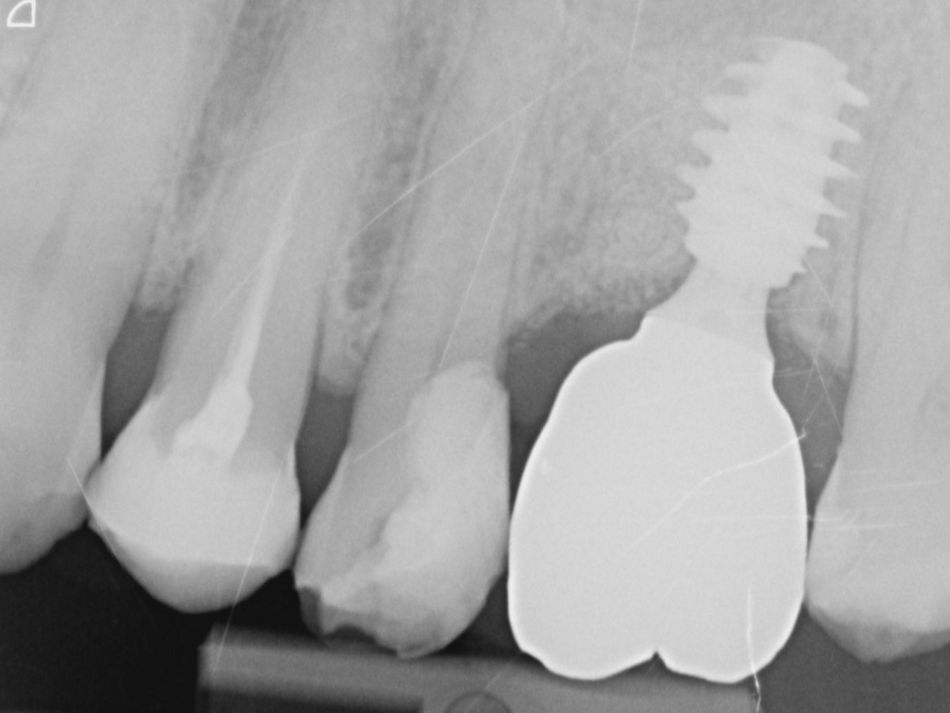

13. Peri-apical radiograph depicting final prosthesis.

13

14a. 14b. Radiograph of 2 years follow-up.

14a

14b